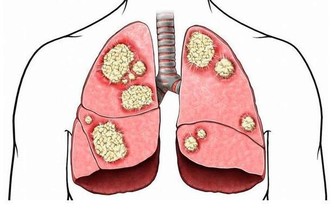

日常生活中,很多人都會出現關節腫痛的問題,高尿酸就是其中的一個原因,如果體內的尿酸過高,就會有大量尿酸結晶,而這些結晶很難排出,只會留在我們的關節中。時間久了,就會出現關節疼痛的現象,這時建議及時去醫院檢查,查明原因,及時調理。